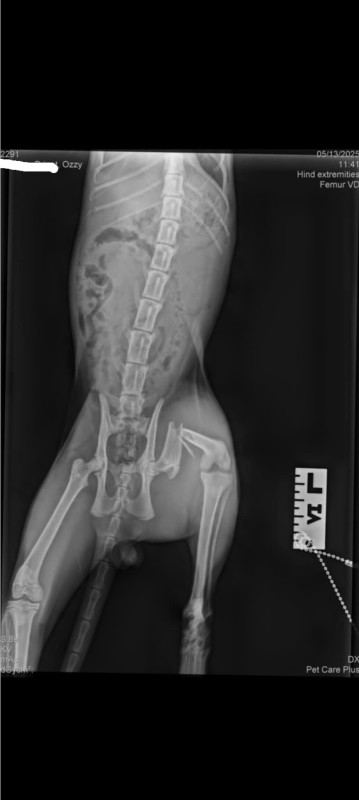

In a world where the bond between humans and animals is cherished, my seven-month-old kitten, Ozzy, has captured my heart with his playful spirit and affectionate nature. Recently, a tragic accident left him with a broken hip, a condition requiring immediate surgical intervention.

As a responsible pet owner, I am acutely aware of the importance of prompt medical care. Unfortunately, the cost of the surgery is significant, and without assistance, I wont be able to afford his surgery.